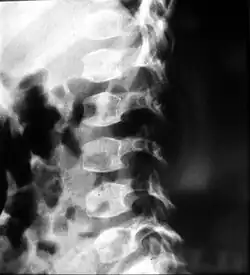

People with spondyloepiphyseal dysplasia are short-statured from birth, with a very short trunk and neck and shortened limbs. Their hands and feet, however, are usually average-sized. This type of dwarfism is characterized by a normal spinal column length relative to the femur bone. Adult height ranges from 0.9 meters (35 inches) to just over 1.4 meters (55 inches). Curvature of the spine (such as kyphoscoliosis and lordosis) progresses during childhood and can cause problems with breathing. Changes in the spinal bones (vertebrae) in the neck may also increase the risk of spinal cord damage. Other skeletal signs include flattened vertebrae (platyspondyly), a hip joint deformity in which the upper leg bones turn inward (coxa vara), and an inward- and downward-turning foot (called clubfoot). Decreased joint mobility and arthritis often develop early in life. Medical texts often state a mild and variable change to facial features, including cheekbones close to the nose appearing flattened, although this appears to be unfounded. Some infants are born with a cleft palate. Severe nearsightedness (high myopia) is sometimes present, as are other eye problems that can affect vision such as detached retinas. About one-quarter of people with this condition have mild to moderate hearing loss.[2]